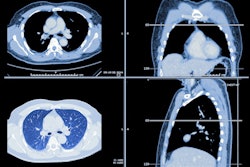

Deep-learning algorithms can effectively segment CT scans of patients with idiopathic pulmonary fibrosis (IPF) and thus offer prognostic information to clinicians, researchers have reported.

The authors tested the use of biomarkers (airway, lung, vascular, and fibrosis volumes) for diagnosis of IPF using deep learning-based segmentation of CT scans and applied them to data from a group of 446 not-yet-treated patients with IPF enrolled in the PROFILE (Prospective Observation of Fibrosis in the Lung Clinical Endpoints) study. They evaluated any relationship between the biomarkers and lung function, disease progression, and mortality. Median follow-up was 39.1 months and cumulative incidence of death was 277, or 62.1%, over five years after diagnosis of IPF.

The deep-learning algorithm successfully segmented 97.8% of the CT images, the team reported. It also found the following: